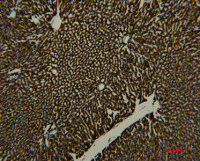

Monoglyceride lipase antibody [HL1938] detects Monoglyceride lipase protein at cell membrane and cytoplasm by immunohistochemical analysis.

Sample: Paraffin-embedded mouse white adipocyte.

Monoglyceride lipase stained by Monoglyceride lipase antibody [HL1938] (GTX637775) diluted at 1:100.

Antigen Retrieval: Citrate buffer, pH 6.0, 15 min